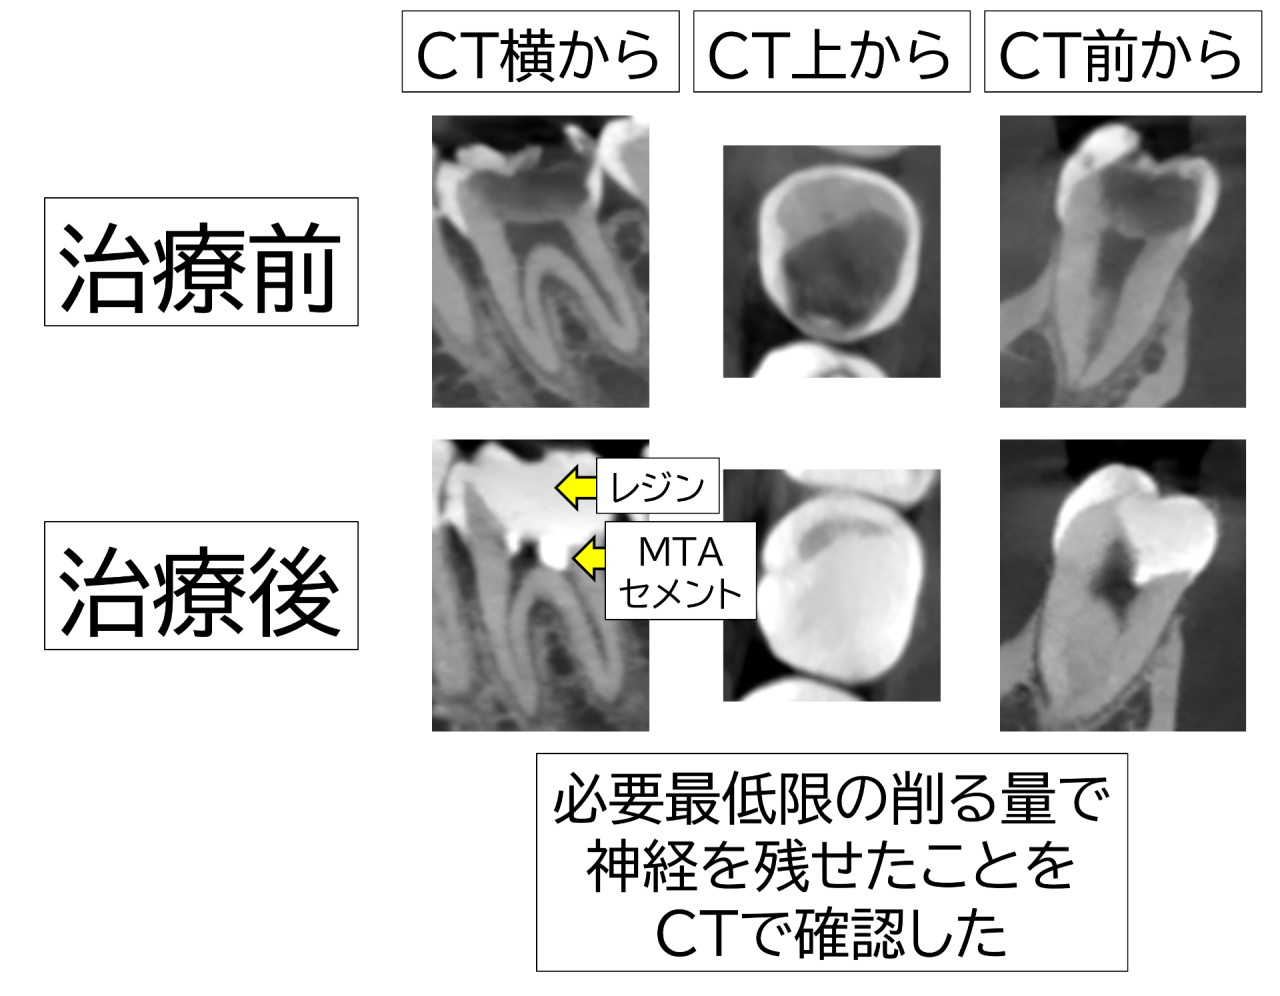

CTのレントゲンでは広く深い大きな虫歯が歯の中心の神経(歯髄)近くまで達している様に見えました。

治療後CTで確認すると、虫歯の範囲をできるだけ超えないように削り、予定通り神経をMTAセメントで保護できていることが確認できました。コンポジットレジンが密にしっかりと詰めていることもわかります。